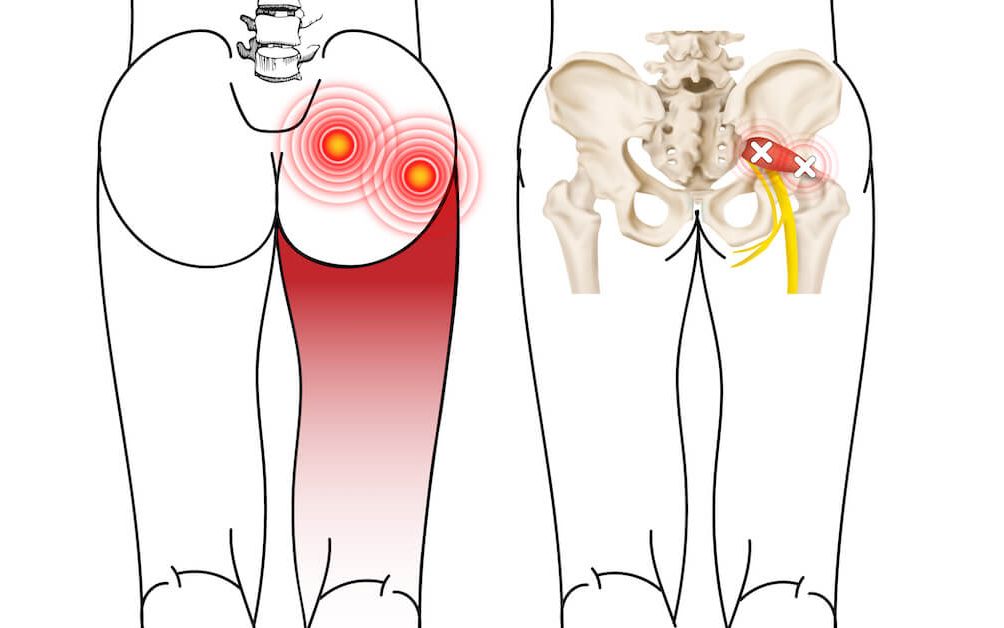

坐骨神经痛,屁股至腿部痛之梨状肌

坐骨神经痛(梨状肌综合征)怎么办? 如何治疗坐骨神经痛 ?

感觉坐骨神经痛,其实是梨状肌综合征,治错就麻烦了

坐骨神经痛?你可能得了梨状肌综合征!